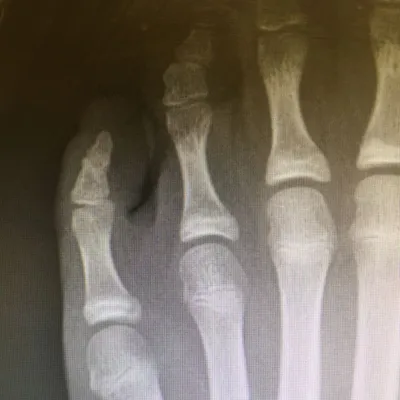

Pediatric Displaced 5th Met Distal shaft/neck fracture

Preop Pics of the displaced fracture prior to Percutaneous Fixation and Reduction

We percutaneously put a pin across the fracture after closed reduction for 12-16 weeks. The last picture is a final after the fracture is healed and the pin is removed.